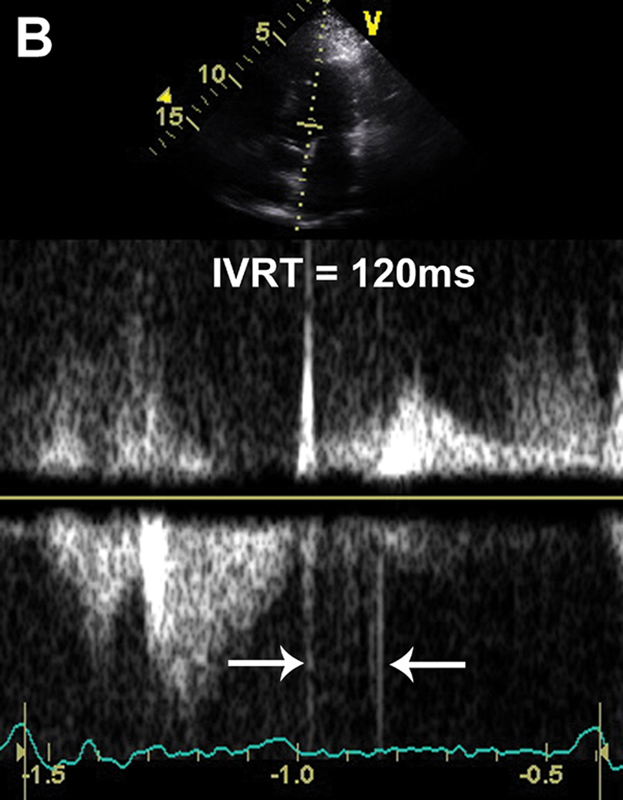

فحوصات تشخيصية لبعض امراض القلب والشرايين التاجية